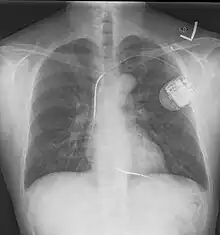

A chest film after insertion of an implantable cardioverter-defibrillator, showing the shock generator in the upper left chest and the electrical lead inside the right heart. Note both radio-opaque coils along the device lead.